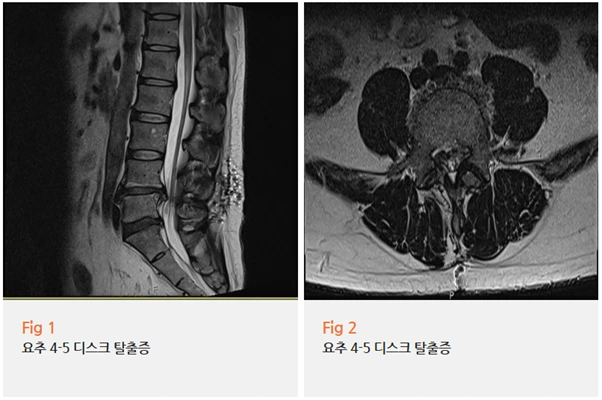

요추 4-5번 추간판탈출증, 즉 허리디스크로 이미 수술을 두 차례나 받으신 분이었거든요.

당일 MRI를 다시 촬영했더니 이전 수술 부위인 요추 4-5번에서 재발성 추간판탈출증이 확인됐어요.

거기에 수술 후 형성된 반흔 조직, 즉 흉터 조직이 신경근 주변에 붙어 있어서

신경 압박이 더욱 심하게 나타나고 있었고요.